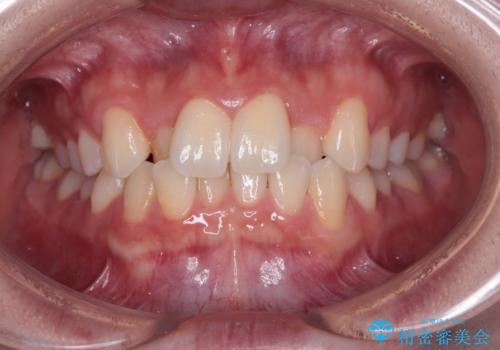

強い咬み込みですり減った前歯 デコボコを抜歯矯正で整える

- 結婚式が近いとのことで、前歯のデコボコを改善したいと来院された患者様です。

口元の突出感はないものの、上顎前歯のデコボコが著しかったため、上顎左右第一小臼歯2本を抜歯することとしました。

咬合力が非常に強く、抜歯したスペースがなかなか閉じないであろうことは予想できましたが、思っていた以上に期間がかかりました。

前歯のすり減りも著しかったため、仕上げの位置の調整にも期間を要しました。